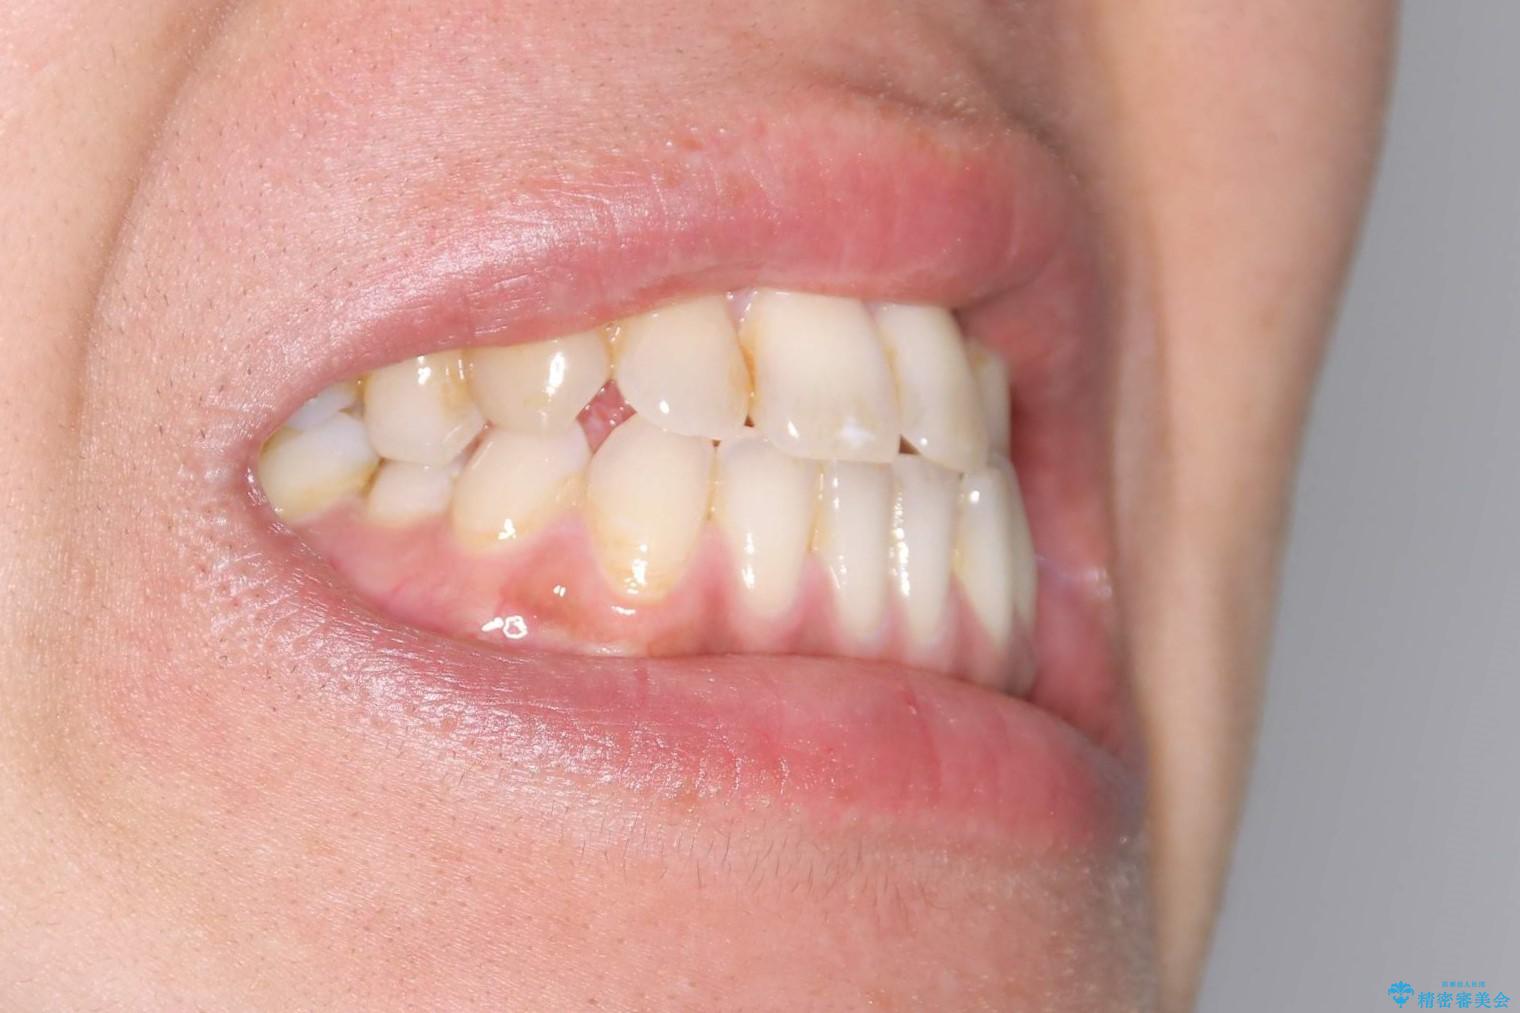

Invisalign インビザライン によるガタつき、受け口傾向の改善

奥歯の位置関係の修正は難儀することが多いマウスピース矯正ですが、割とスムーズに奥歯の位置関係の修正をすることができました。

クロスバイトもきれいになり、きれいな歯並びとなりました。